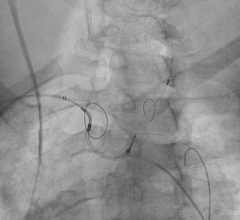

While transcatheter aortic valve replacement (TAVR) is a paradigm shift in how valve disease is treated, one nagging ...

January 28, 2014 — Claret Medical Inc. received CE marking for the Sentinel Cerebral Protection System (CPS) for embolic ...

November 1, 2011 – Claret Medical Inc. said its Montage System has received CE mark approval as the world's first ...